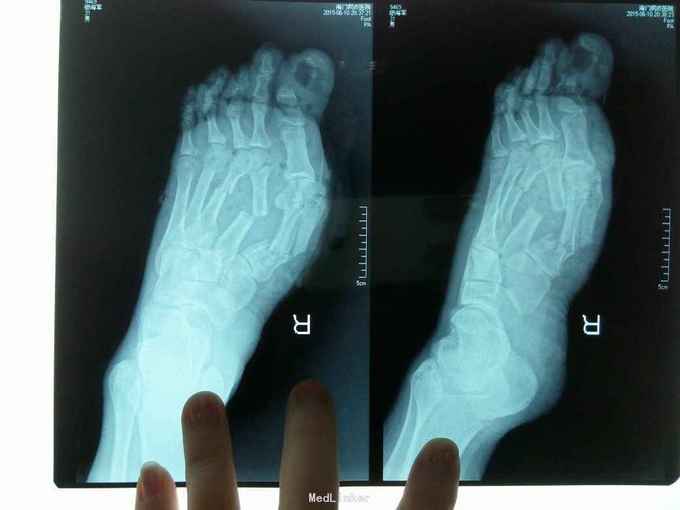

砸伤致右足疼痛、出血1小时 患者自诉1小时前在工作中不慎被1.5吨重物砸伤右足,当即伤足疼痛,流血不止,被同事急送我院就诊。

右足外观肿胀明显,局部大面积瘀紫,第一跖骨背侧可见一不规则伤口,创缘不齐,创口内可见骨折断端外露,踇趾末节大部分毁损,仅少许趾腹存留,各伤口出血活血,污染挫伤重。 拍片示:右足第1-4跖骨骨折,第1跖趾关节脱位,踇趾末节粉碎性骨折伴骨、软组织缺损,第4、5趾末节骨折。